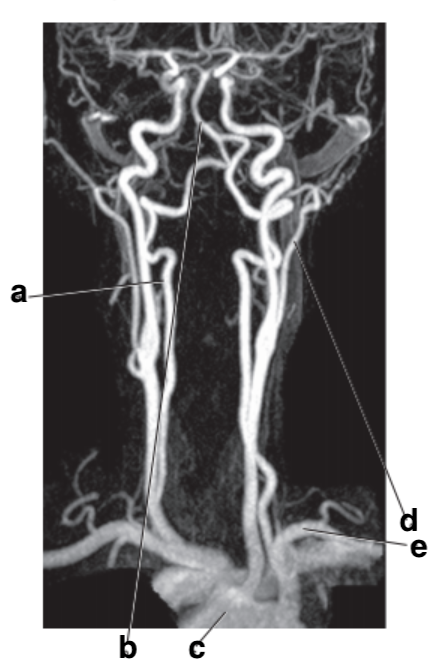

Which letter is the popliteal artery?

A

Which letter is the left common carotid?

Which letter is the Right vertebral artery?

f

Common carotid artery

left popliteal artery